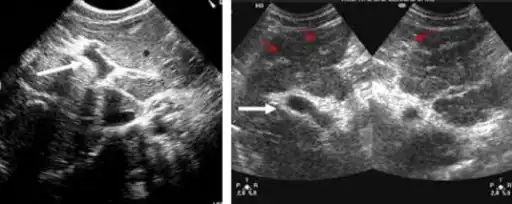

-

Ultrasonographic images in hepatic schistosomiasis -